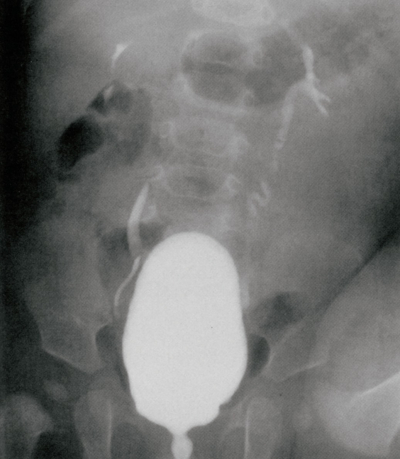

尿所見:蛋白 1+、沈渣に赤血球 5-8/HPF、白血球 30-50/HPF。血液所見: 赤血球 430万、Hb 12.3 g/dL、Ht 38%、白血球 13,800。血液生化学所見:尿素窒素 10 mg/dL、クレアチニン 0.9 mg/dL。排尿時膀胱尿道造影写真を別に示す。

考えられるのはどれか。

d. 膀胱尿管逆流